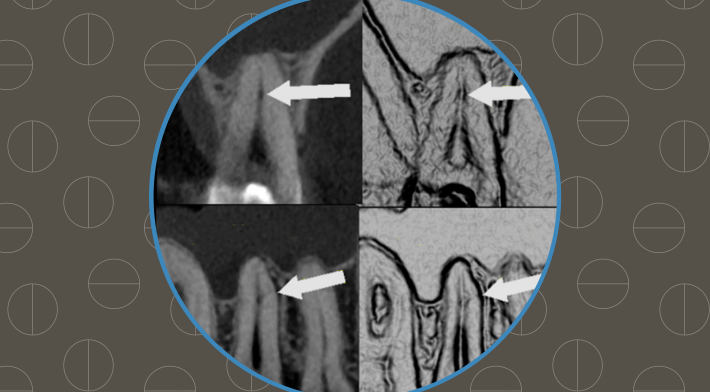

Radiologia em foco: Diagnóstico eficiente para fratura dentária

Escolher a clínica de radiologia certa, faz toda diferença no sucesso de seus diagnósticos.